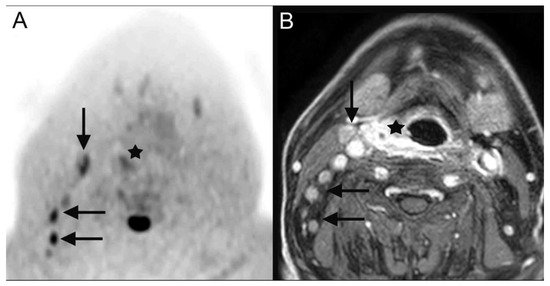

| 28 | hypopharyngeal carcinoma (Figure 2) | pT2 pN2b cM0 | squamous cell carcinoma |

| 28 | hypopharyngeal carcinoma (Figure 2) | primary chemoradiotherapy |